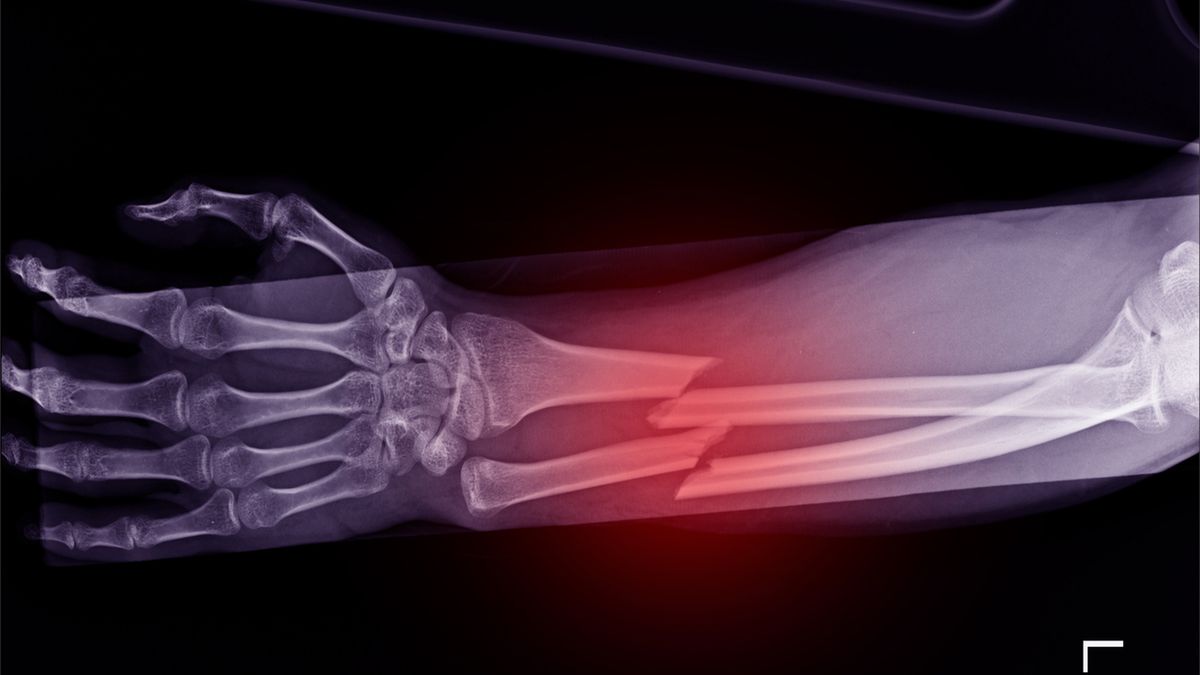

Złamania kości przedramienia

Gdy mówimy o kościach przedramienia, mamy na myśli kość łokciową i promieniową. Kości te leżą względem siebie równolegle. Podczas poruszania ręką, kości te krzyżują się. Złamania kości przedramienia mogą obejmować obie kości lub tylko jedną z nich. Towarzyszyć temu może zwichnięcie jednej kości w stawie łokciowym lub nadgarstkowym. Do złamania kości przedramienia dochodzi przy urazie bezpośrednim lub podczas upadku na wyciągniętą i osłabioną kończynę.

Złamania kości promieniowej powstają zazwyczaj w okolicy trzonu kości bądź w okolicy nadgarstka.Złamania kości promieniowej powstają zazwyczaj w okolicy trzonu kości bądź w okolicy nadgarstka.

Złamania kości przedramienia są niezwykle trudne w leczeniu. W obrębie przedramienia często spotyka się złamania kości promieniowej w odcinku dalszym, nazwane złamaniem w miejscu typowym lub złamaniem Colles'a. Charakteryzuje się bagnetowatym ustawieniem nadgarstka, bolesnością i obrzękiem tej okolicy.

Złamania kości promieniowej powstają zazwyczaj w okolicy trzonu kości bądź w okolicy nadgarstka. Urazy trzonu kości promieniowej przyczyniają się do uszkodzenia stawu promieniowo-łokciowego. Leczenie polega na unieruchomieniu ręki w gipsie, przez nieco ponad miesiąc (do 6 tygodni). Powikłaniem tego złamania mogą być nietypowe skurcze mięśni, które pojawiają się tuż po zdjęciu gipsu. Złamania tego typu są niezwykle niebezpieczne i wymagają długiego leczenia.